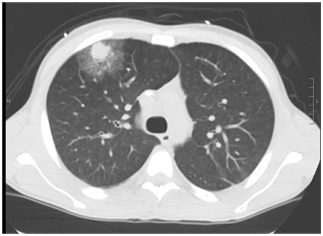

The timely diagnosis of invasive pulmonary aspergillosis is incredibly important. Non-invasive modalities of diagnosis such as beta-D glucan and galactomannan can take a few days to come back and much of the time, we rely on chest imaging to guide treatment decision. The classic finding that has been attributed to invasive pulmonary aspergillosis has been the halo sign, which is an area of consolidation surrounded by ground glass:

They note the halo sign preceded the development of typical cavitation or air crescent by at least 2-3 weeks and typically the progression went from “halo” to cavitation. A small number of patients, but the takeaway was that invasive pulmonary aspergillosis could look like anything.